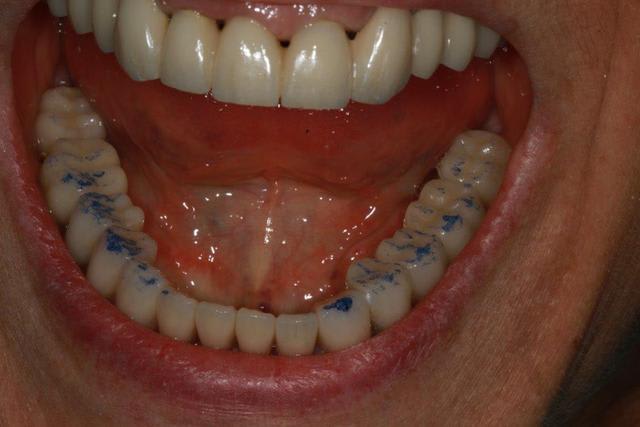

pose des antérieurs mandibulaire et j'aimerais ton avis enlaye sur les contacts ...

Img 2273 rnmdjy - Eugenol

Img 2274 dghozk - Eugenol

Img 3578 oj0dv7 - Eugenol

Img 3581 rkwl1n - Eugenol

Img 3582 vqzsho - Eugenol

11/02/2016 à 00h52

ah voila ça se précise .

d'abord j'ai besoin de 2 précisions :

1- cet enregistrement est il manipulé ? ( centrée et ou lateralités )

2- quelles sont les dents solidarisées du bas ? (surtout bloc ant )

on va considerer que ce n'est pas un enregistrement manipulé .et puisque tu me demandes mon avis , je te dis comment je ferais , mais bien sur cela ,n'engage que moi ,hein !

Eh bien ,ç est pas mal ,et il y a 2 trucs qui sont pratiques :

- une absence de contact sur le bord libre des incisives du bas

- un contact léger sur les 7

ces 2 trucs ensembles font que l'on a de la marge pour retoucher au cas où ,et là ,tu en as de la marge :-)

1- , vu que le haut est tout solidarisé , le nombre de points n'est pas très important .ce qui est important ,ç est l'incidence que peuvent avoir ces points sur les dents unitaires du bas .( d'où ma question ,sur les dents solidarisées )

2- ,si retouche on doit faire , on commencera par retoucher , les points où tu vois un point blanc au milieu .

ce point blanc ,veut dire que le point est tellement fort ,que le papier en a essuyé le centre .par la suite s'il y a une grande surface , on arrondira en partant du centre de cette surface , pour privilégier des formes convexes et non concaves .

3- , les points ne donnent aucune information en soit s'ils ne sont associés avec l'interrogatoire du patient ;

par exemple , la 1ere chose à demander est :

où est le 1er contact ( à droite à gauche ...) ? évidemment on commencera par retoucher le 1er contact s'il y a lieu .

si on ne pose pas la question ,bien , on ne peut pas connaître l'ordre des points .

or , ce n'est pas tellement les points qui nous intéresse ,mais l'ordre dans lequel ils se font . ce qui est logique puisqu'il y a quand même des mouvement lors de la fermeture ,ou plutôt pour arriver à la fermeture .

voila grosso modo comment je vois l 'intérêt des points bleus dans un cas comme le tien , et si tu veux je peux aller plus loin sur ton cas .